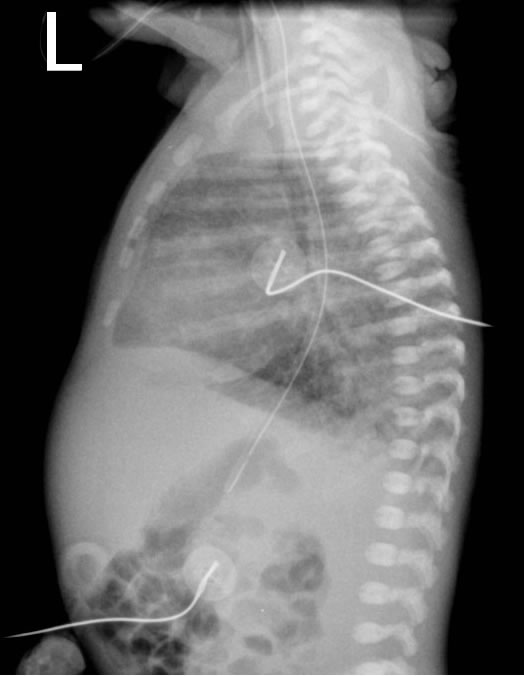

-The chest radiograph appearances of pneumonia are not specific, and frank lobar consolidation as seen in adults and older children is rare. More commonly, there is coarse opacity of one or more regions of the lung parenchyma. However, these appearances can also be seen with retained fetal lung fluid, meconium aspiration, aspiration of gastric contents, and pulmonary haemorrhage. Pleural effusions are not uncommon in infection, but again may be seen with other conditions.-Group B Streptococcus can have an appearance similar to Respiratory Distress Syndrome (Surfactant Deficiency), although the granulation is typically more coarse.